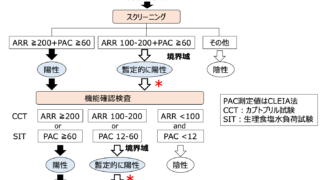

診断基準

神戸大学のグループが提唱している診断基準は

①後天的なGH・PRL・TSHの特異的な欠乏

内分泌学的所見では、GH・PRLが検出下限以下で、TSH・IGF-1・fT4が低値を示す。

負荷試験でこれらのホルモンの反応が悪い。

他の下垂体ホルモンの分泌の障害がない。

Probable:診断基準①を満たす

Definite:診断基準①と②を満たす

注釈:診断基準③は診断の助けとなるが、内分泌学的異常の診断時には必ずしも明らかではない。